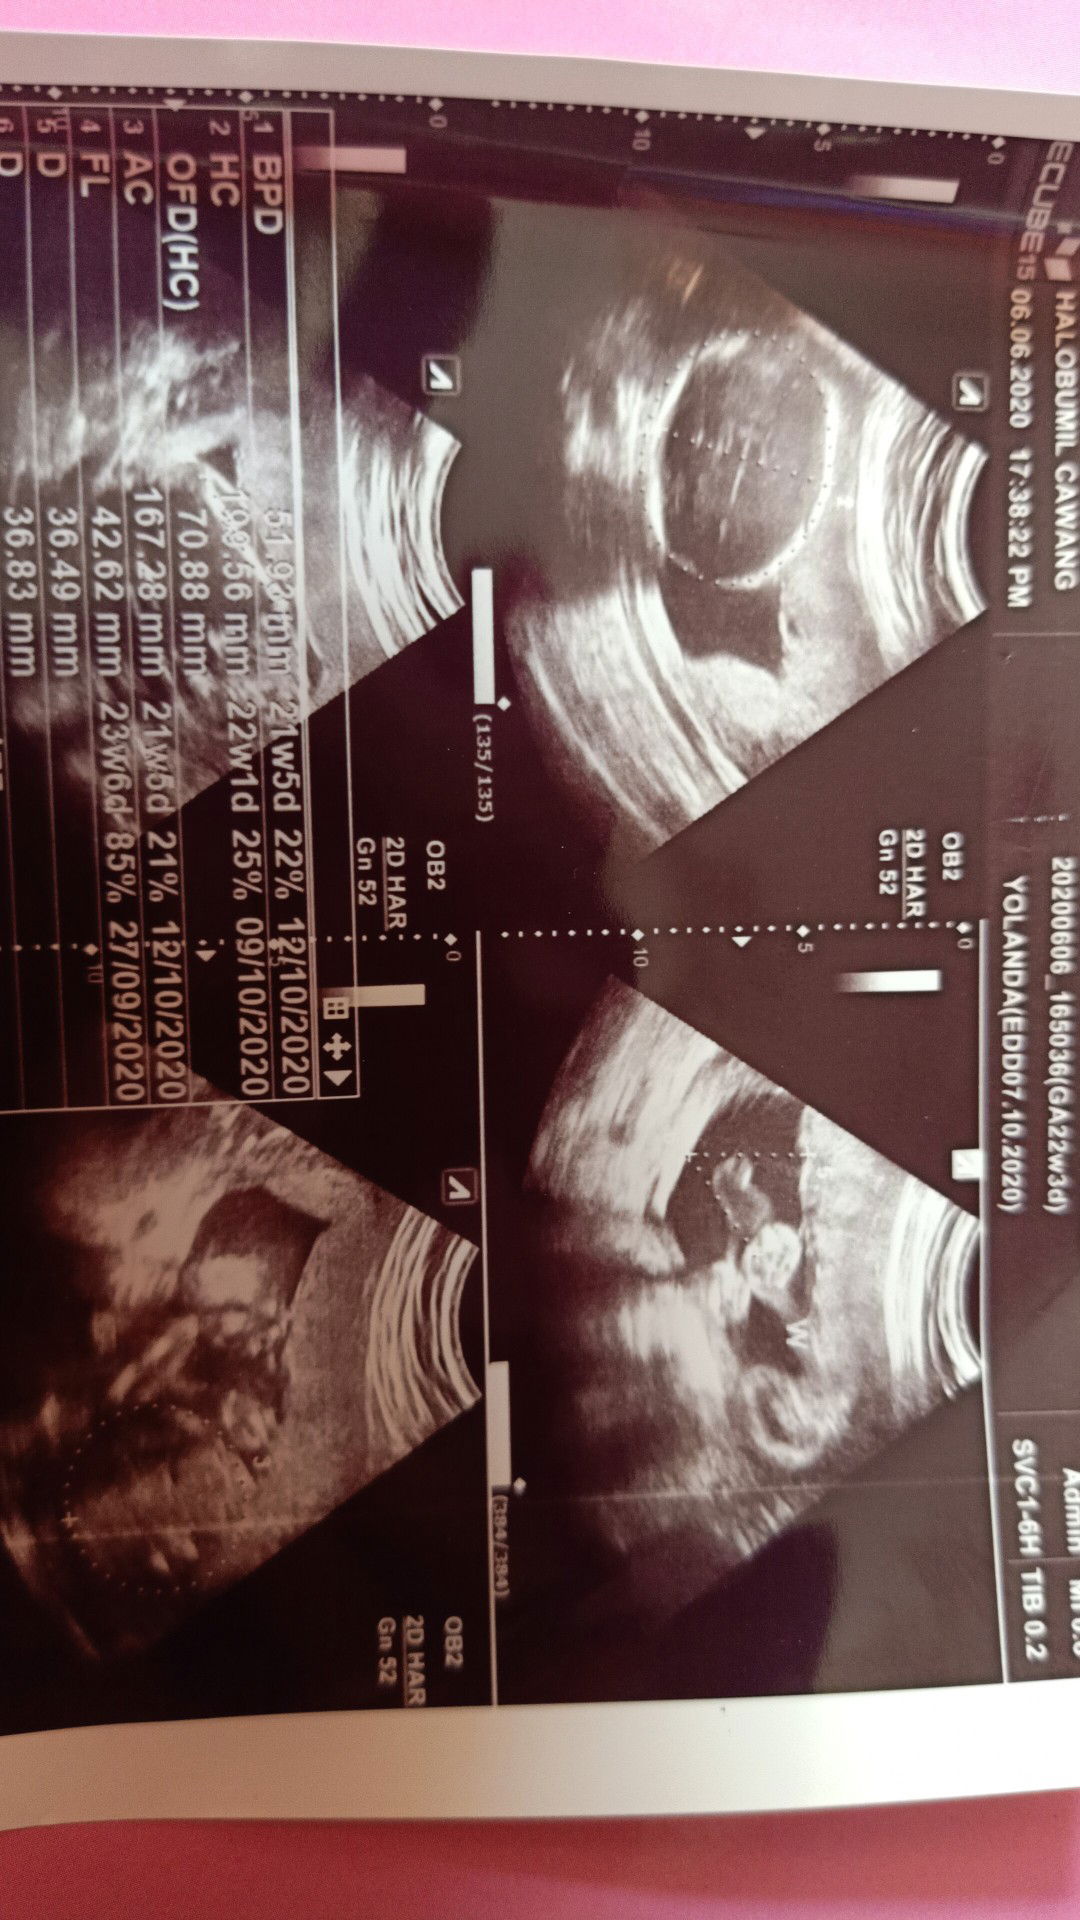

usg

Ini baca usgnya gimana ya kurang paham

Coba googling bunda. Istilah2 usg gtu. Terus bunda cocokin usia kandungan nya sesuai gak sama HPL dr HPHT dan HPL dr USG. Ini berdasarkan pengalaman ku ya bun, soalnya dulu anakku ga cocok. Ternyata dia BBLR